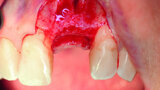

Fig. 3: After the extraction, the apical granulation tissue was excochleated.